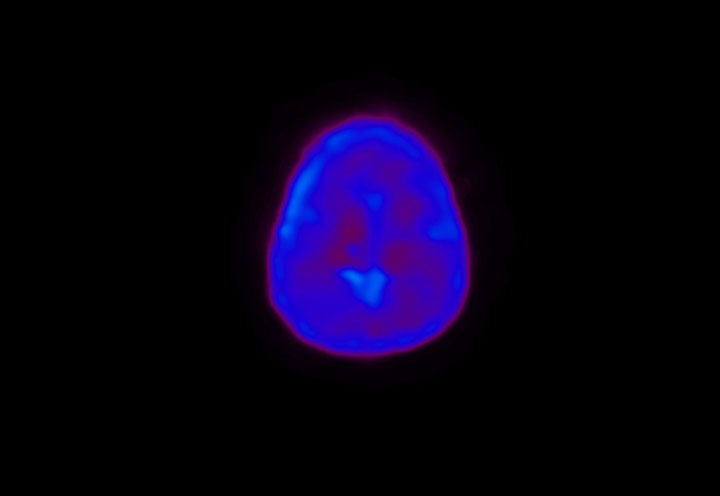

Head / Case4 : Amyloid

Sagittal

Courtesy : Kindai University Hospital

- Imaging protocol

- Injected dose: 3.21 MBq/kg, 18F-Flutemetamol

- Uptake time: 100 minutes

- Scan time: 20 minutes